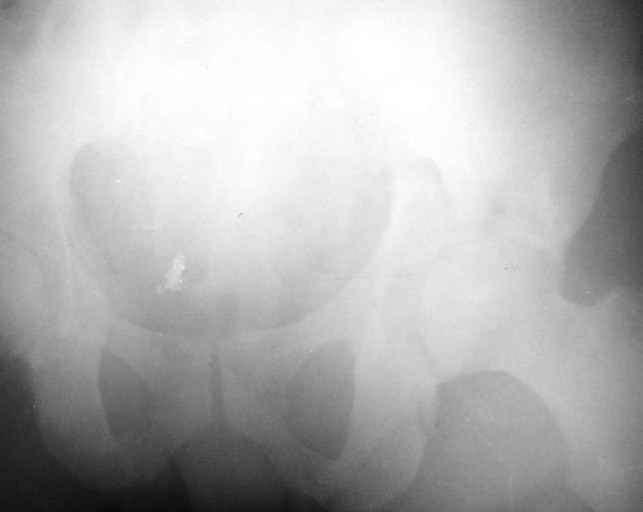

Сегодня на приеме был пациент, чьи начальный снимок напомнил обсуждаемый сейчас (см. выше). Снимки в других проекциях, показывающие истинный характер повреждения, ниже. Это inlet проекция (вход в таз) и запирательная проекция Judet.

1

2